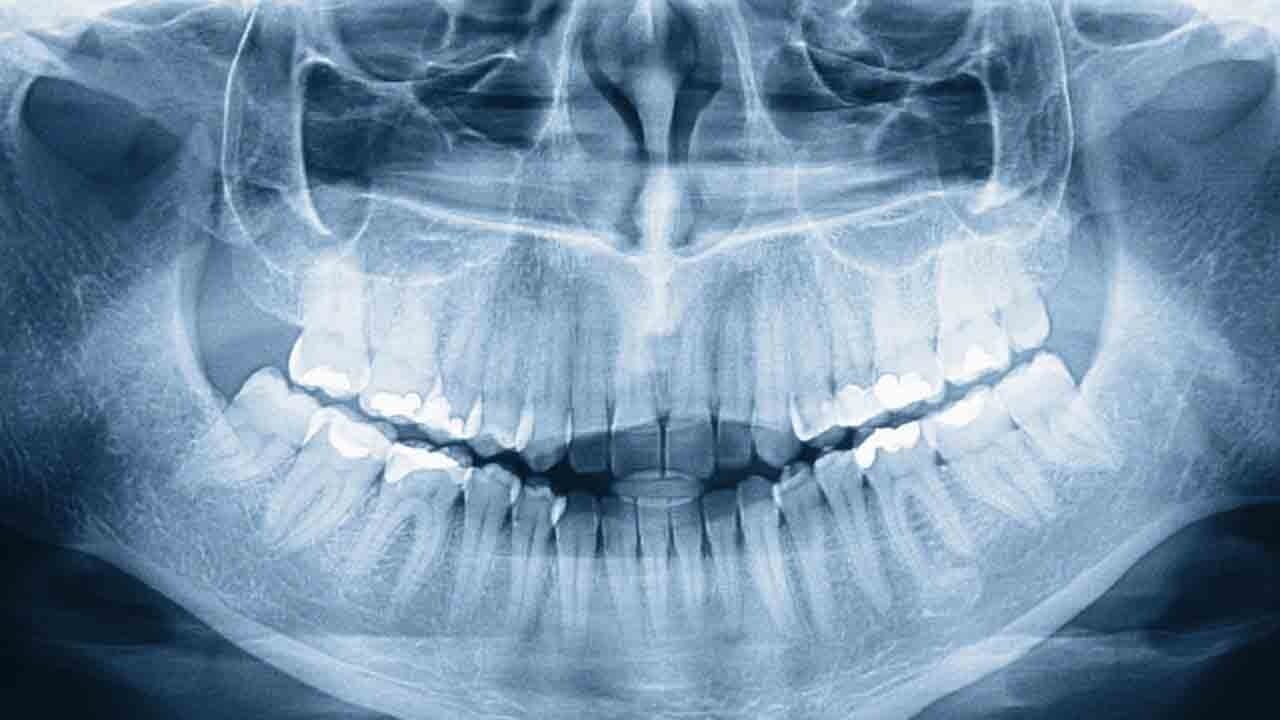

Muniandy, 2021 yılındaki bir yemekte dişlerini saydığında ağzında tam 38 diş olduğunu fark etti. Şüphe üzerine çekilen diş röntgeni ise asıl sürprizi ortaya çıkardı; henüz yüzeye çıkmamış dört diş daha diş etlerinin altında bekliyordu. 2023 yılının başlarına gelindiğinde Muniandy, toplamda 42 dişe ulaşarak standart bir insandan 10 diş daha fazlasını barındıran bir ağız yapısına sahip oldu. İlginç olan ise, bu kadar fazla dişin herhangi bir sağlık sorunu yaratmadan, büyük oranda düzgün bir şekilde dizilmiş olmasıydı. Muniandy, kendisi söylemediği sürece kimsenin bu farkı anlamadığını, sadece temizlik ve bakım için biraz daha fazla çaba sarf ettiğini belirtiyor.

HİPERDONTİ: NADİR GÖRÜLEN GENETİK BİR MİRAS

Diş sayısındaki bu fazlalık, toplumun yaklaşık %0,1 ile %3,8'i arasında görülen nadir bir durum. Uzmanlar, bu tablonun genellikle genetik faktörlerden veya anne karnındaki gelişim sürecinde dişlerin oluştuğu hücrelerdeki bir düzensizlikten kaynaklandığını söylüyor. Diş hekimi Ollie Jupes'e göre, eğer bu fazla dişler estetiği bozmuyor veya ağız fonksiyonlarını engellemiyorsa onlara dokunmaya gerek yok. Ancak her vaka Muniandy kadar şanslı ilerlemiyor. Dişlerin çene yapısını bozması, temizliği zorlaştırarak çürüğe yol açması veya çene eklemlerinde fonksiyon kaybı yaratması durumunda cerrahi müdahale kaçınılmaz bir yol halini alıyor.

Muniandy erkekler kategorisinde rekoru elinde tutsa da, tıp literatüründe çok daha uç vakalar mevcut. Örneğin 2011 yılında 11 yaşındaki bir kız çocuğunda, genetik bir bozukluk sonucu toplamda 81 diş saptandı. Süt dişleri ve kalıcı dişlerin arasına sıkışmış 31 fazla dişin bulunduğu bu tip durumlarda, çene kemiğinin bütünlüğünü bozmadan bu dişleri çekmek uzmanlar için oldukça riskli ve zorlu bir süreç. Bu dişlerin birçoğu şekil bozukluğuyla geldiği için onları normal bir diş dizisine dahil etmek de pek mümkün değil. Genellikle bir çocukluk dişi döküldüğünde veya rutin bir kontrol sırasında tesadüfen ortaya çıkan bu durum, vücudun hazırladığı karmaşık sürprizlerden biri...